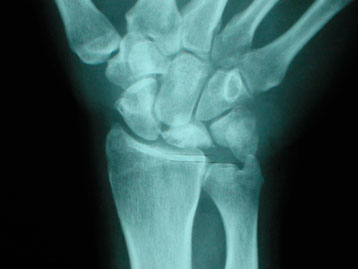

Alteraciones mecánicas o anatómicas, como una discrepancia en la longitud de los huesos: tener un cúbito corto (figuras 1 y 2) y una determinada forma anatómica de semilunar (tipo I) (figura 3).

Figura 3: tipos de formas del semilunar. Mayor riesgo el tipo I con cúbito corto